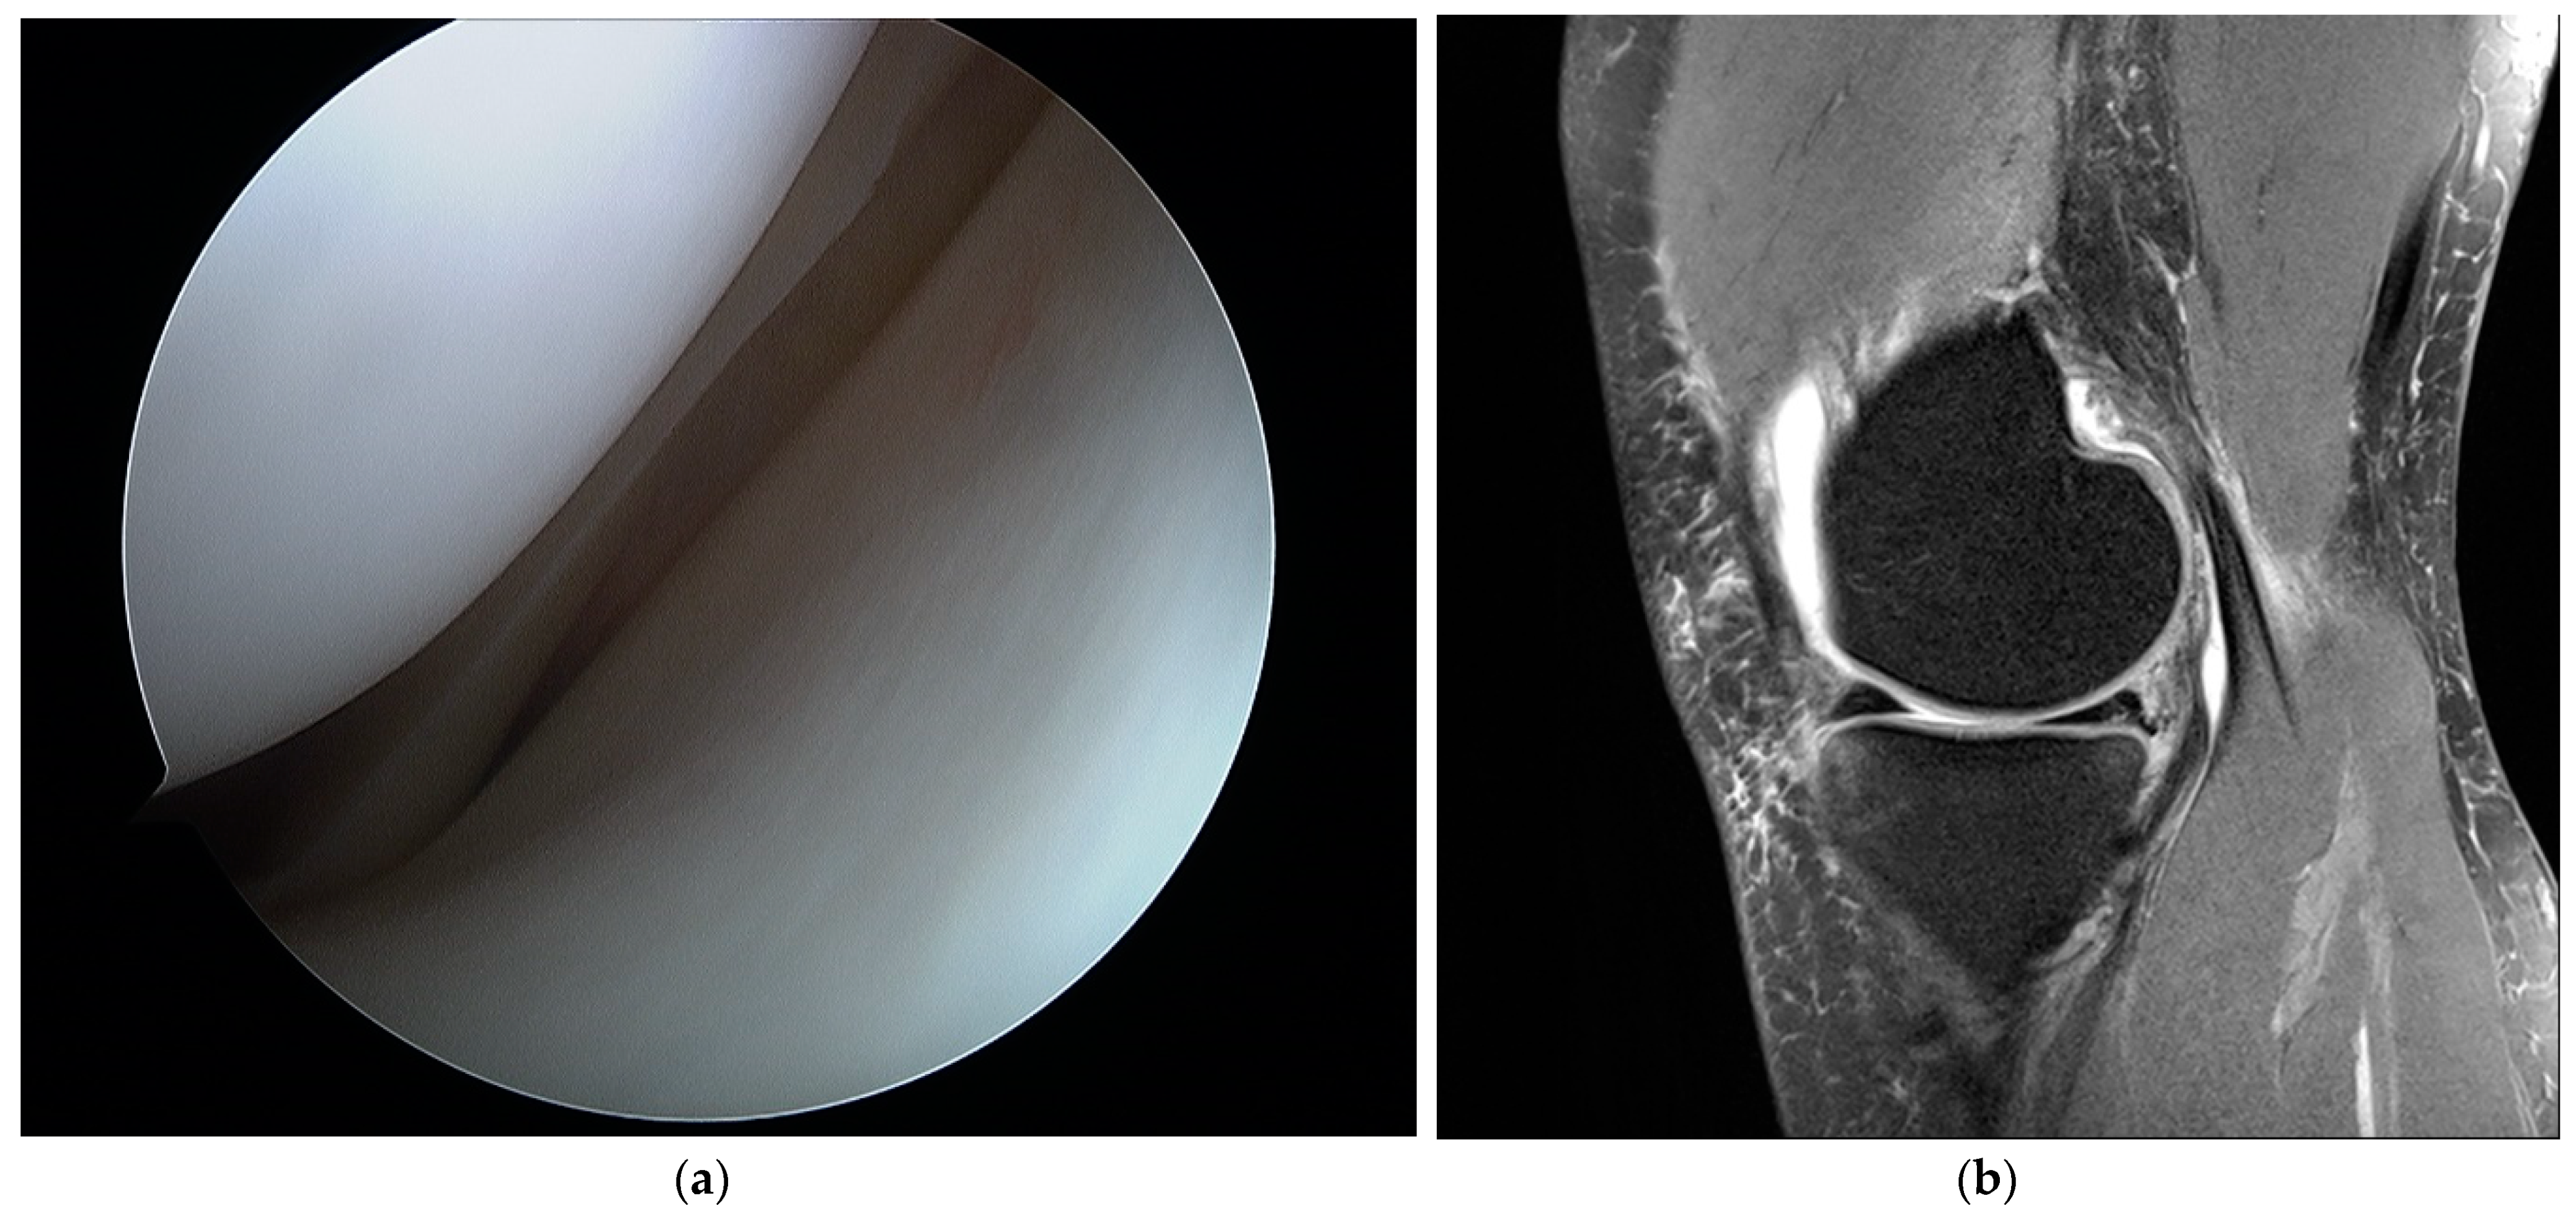

2. Materials and Methods

3. Results

4. Discussion